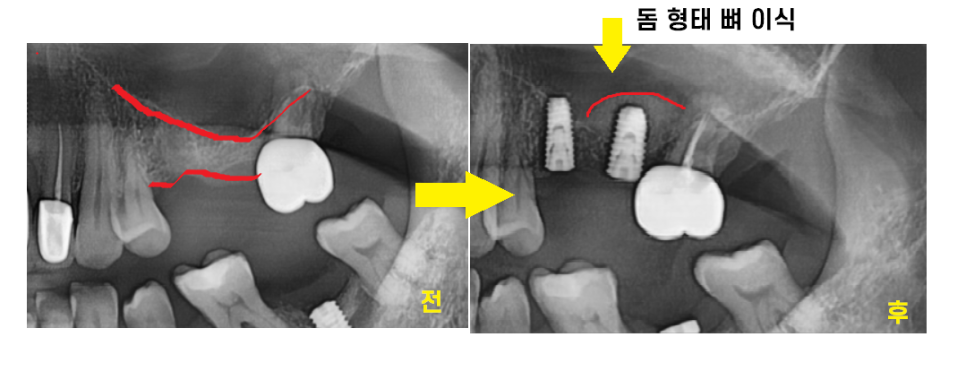

23.05.20

상악동 거상술을 동반한

상일동 임플란트 완료 사진입니다.

뼈가 월드컵 경기장 모양처럼

돔 형태로 이식이 된 게 확인됩니다.

이제 임플란트가 뼈에 잘 붙기를

기다리는 시간만 남았습니다.

환자분에 따라 치유 기간은 다르지만

상악동 거상술을 한 경우 적어도 4개월,

길게는 6~8개월까지의 시간을 기다립니다.

수술 전후 차이 한 장으로 보여드릴게요~

뼈가 이식된 것이 보이시죠?

상악동 거상술 수술이 잘 되었습니다.